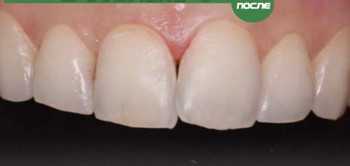

Белоконова Анна Андреевна принимает в «Стоматология ЯБЛОКО'В» в Санкт-Петербурге. Стаж 16 лет. Специализируется на терапии, гигиене полости рта, детской стоматологии и пародонтологии, по которым клиника оказывает 21 услугу. Имеет 2 работы до/после в портфолио. Для уточнения дополнительной информации о специалисте или записи на прием можно позвонить по телефону

2 работы в портфолио